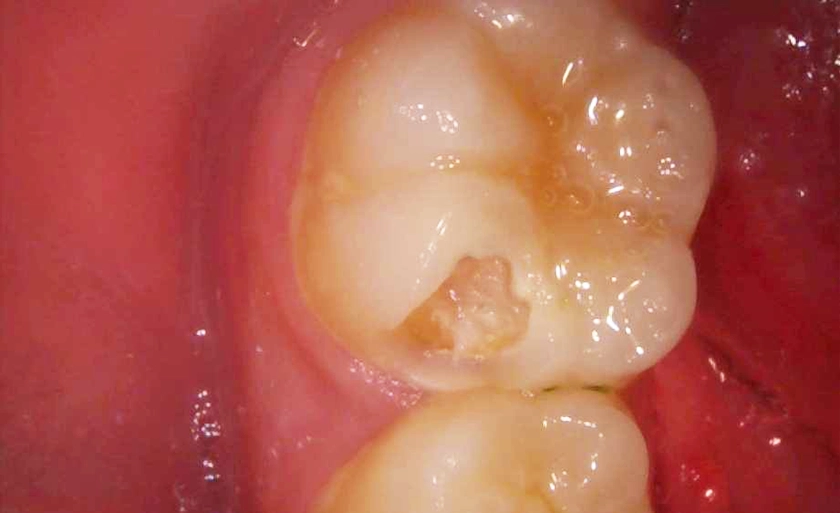

③虫歯を取り切った状態です。穴の中に赤い部分があります。これが歯の神経で、完全に露出してるのが分かると思います。従来の治療法だと神経を抜く治療をしてましたが、今回は神経を残す治療をしていきます。

④炎症のある神経を2ミリほど除去し、MTAセメントを詰めました。白くなってる部分がMTAセメントです。